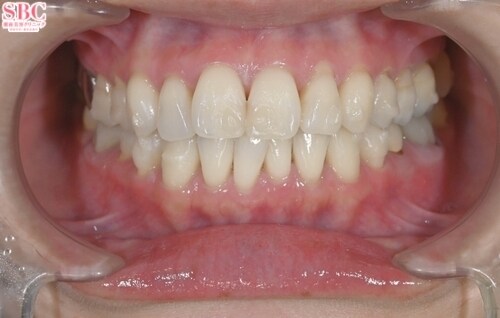

施術後8ヶ月後

「前歯の捻じれ、歯の重なりがきになる」とのことでインビザラインモデレートにて治療したお写真になります★約7か月ほどできれいに並びました!マウスピース矯正は一日20時間以上マウスピースを使用し1週間?10日位の交換で進めていきます。スペースが足りない場合はIPR(歯と歯の間を削ってスペースを作る処置)やゴムかけが必要になる場合がございます。どのプランが適切かカウンセリング時にご説明させていただきます★ご興味ある方は是非カウンセリングにいらしてくださいませ。お待ちしております!

「前歯の捻じれ、歯の重なりがきになる」とのことでインビザラインモデレートにて治療したお写真になります★

約7か月ほどできれいに並びました!

マウスピース矯正は一日20時間以上マウスピースを使用し1週間?10日位の交換で進めていきます。

スペースが足りない場合はIPR(歯と歯の間を削ってスペースを作る処置)やゴムかけが必要になる場合がございます。

どのプランが適切かカウンセリング時にご説明させていただきます★